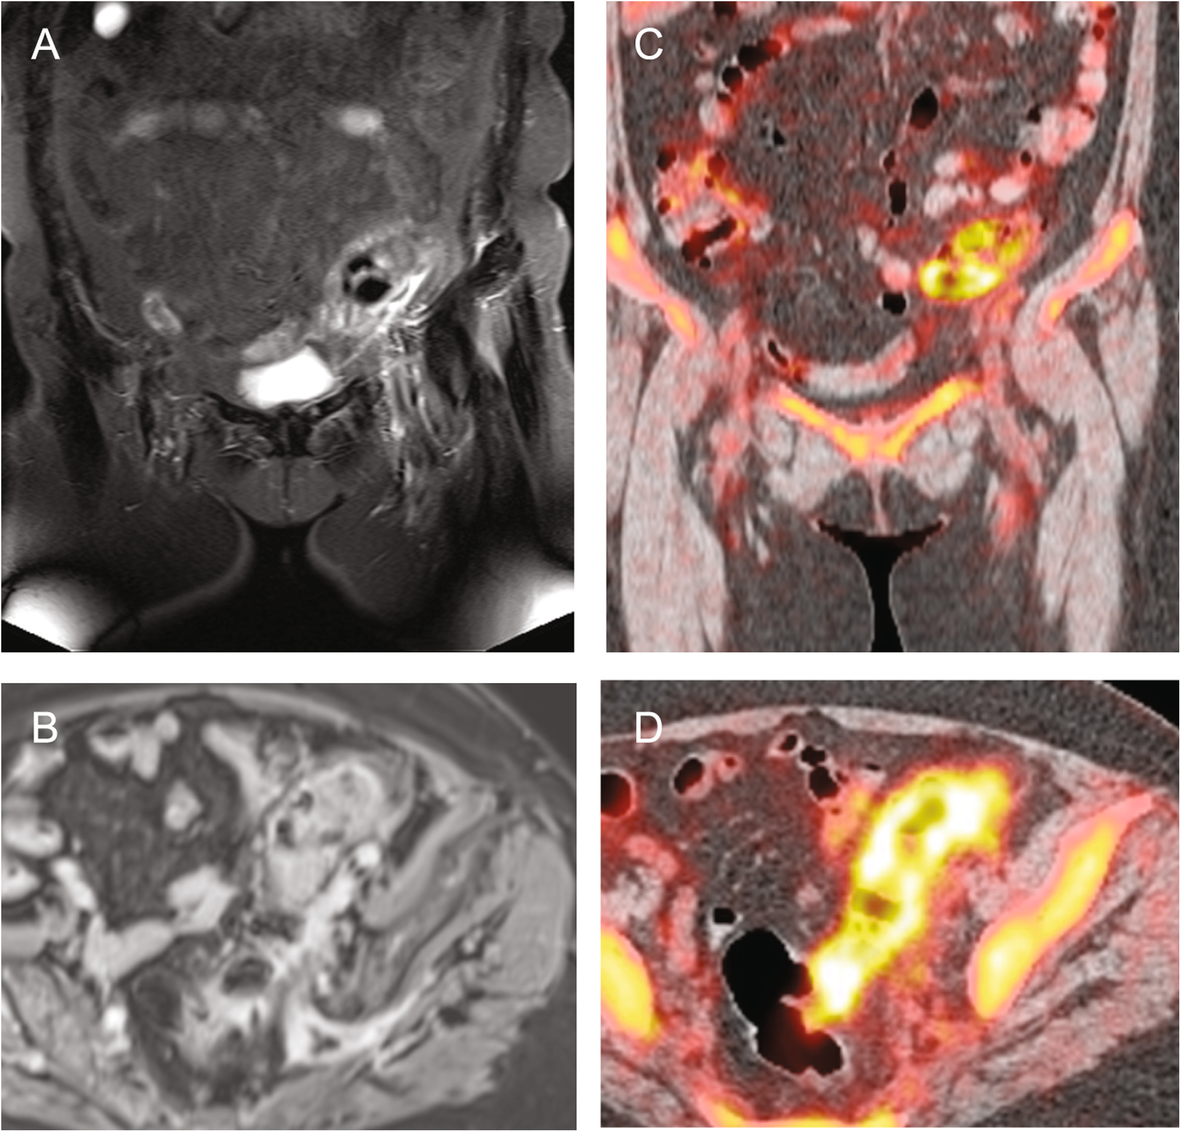

Fig. 3

76-year-old patient with FUO suffering from occult sigmoid diverticulitis who underwent both wb-MRI and PET-CT. Coronal T2-STIR a and axial contrast enhanced T1-VIBE b images reveal sigmoid wall edema and perifocal fat-stranding in accordance with sigmoid diverticulitis. Coronal and axial FDG-PET-CT c, d display elevated tracer uptake of the sigmoid as sign of acute inflammation